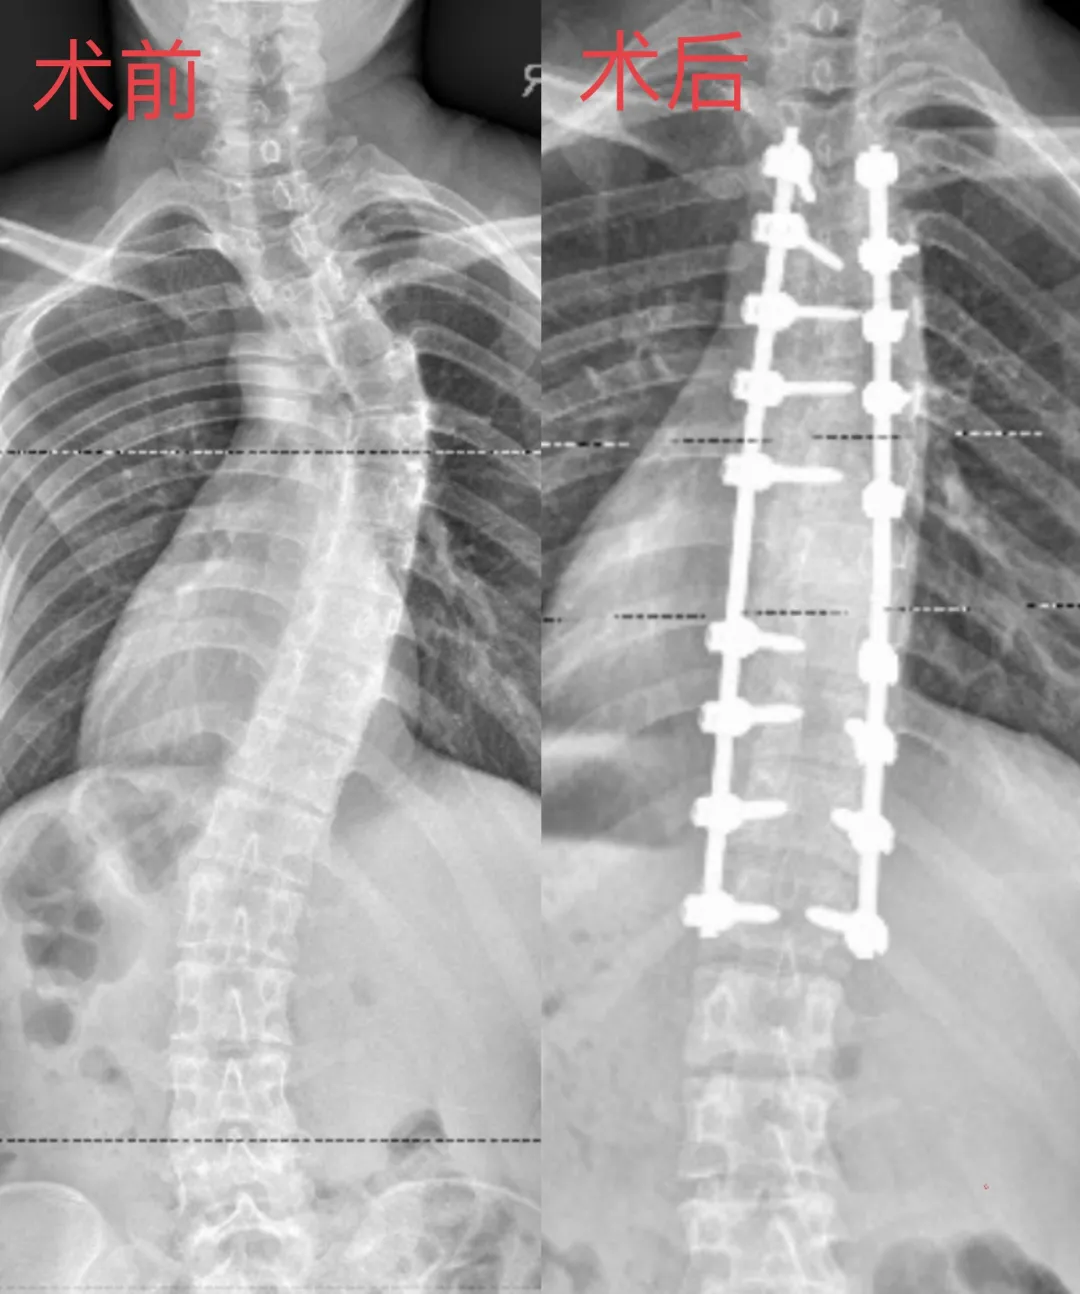

近日,广西医科大学第一附属河池医院·河池市人民医院脊柱骨病外科团队运用“骨科手术机器人”为21岁脊柱侧弯患者完成高难度矫正手术。这名因神经纤维瘤病导致脊柱严重变形的姑娘,术后不仅身高增加了5厘米,体态恢复挺拔,更重拾了生活信心。

手术过程顺利,术后患者恢复状况良好,仅两周时间,患者脊柱侧弯角度大幅改善。她站立时肩膀平衡度提高,体态改观显著。摸着笔直的脊梁,姑娘激动地说:“背直了,肩膀也对称了,终于可以自信地穿上喜欢的衣服了。”

脊柱骨病外科专家介绍,天玑II代机器人辅助手术为复杂脊柱侧弯矫正提供了更精准、更安全的解决方案。术前,医生会用三维影像重建为患者“量体裁衣”,制定专属矫正方案。手术机器人的“透视眼”更是能辅助在骨骼畸形处精准打入螺钉,误差不到1毫米,减少神经损伤风险;还能智能计算截骨角度,确保矫正一步到位。整个过程创口小、出血少,手术时间大大缩短。